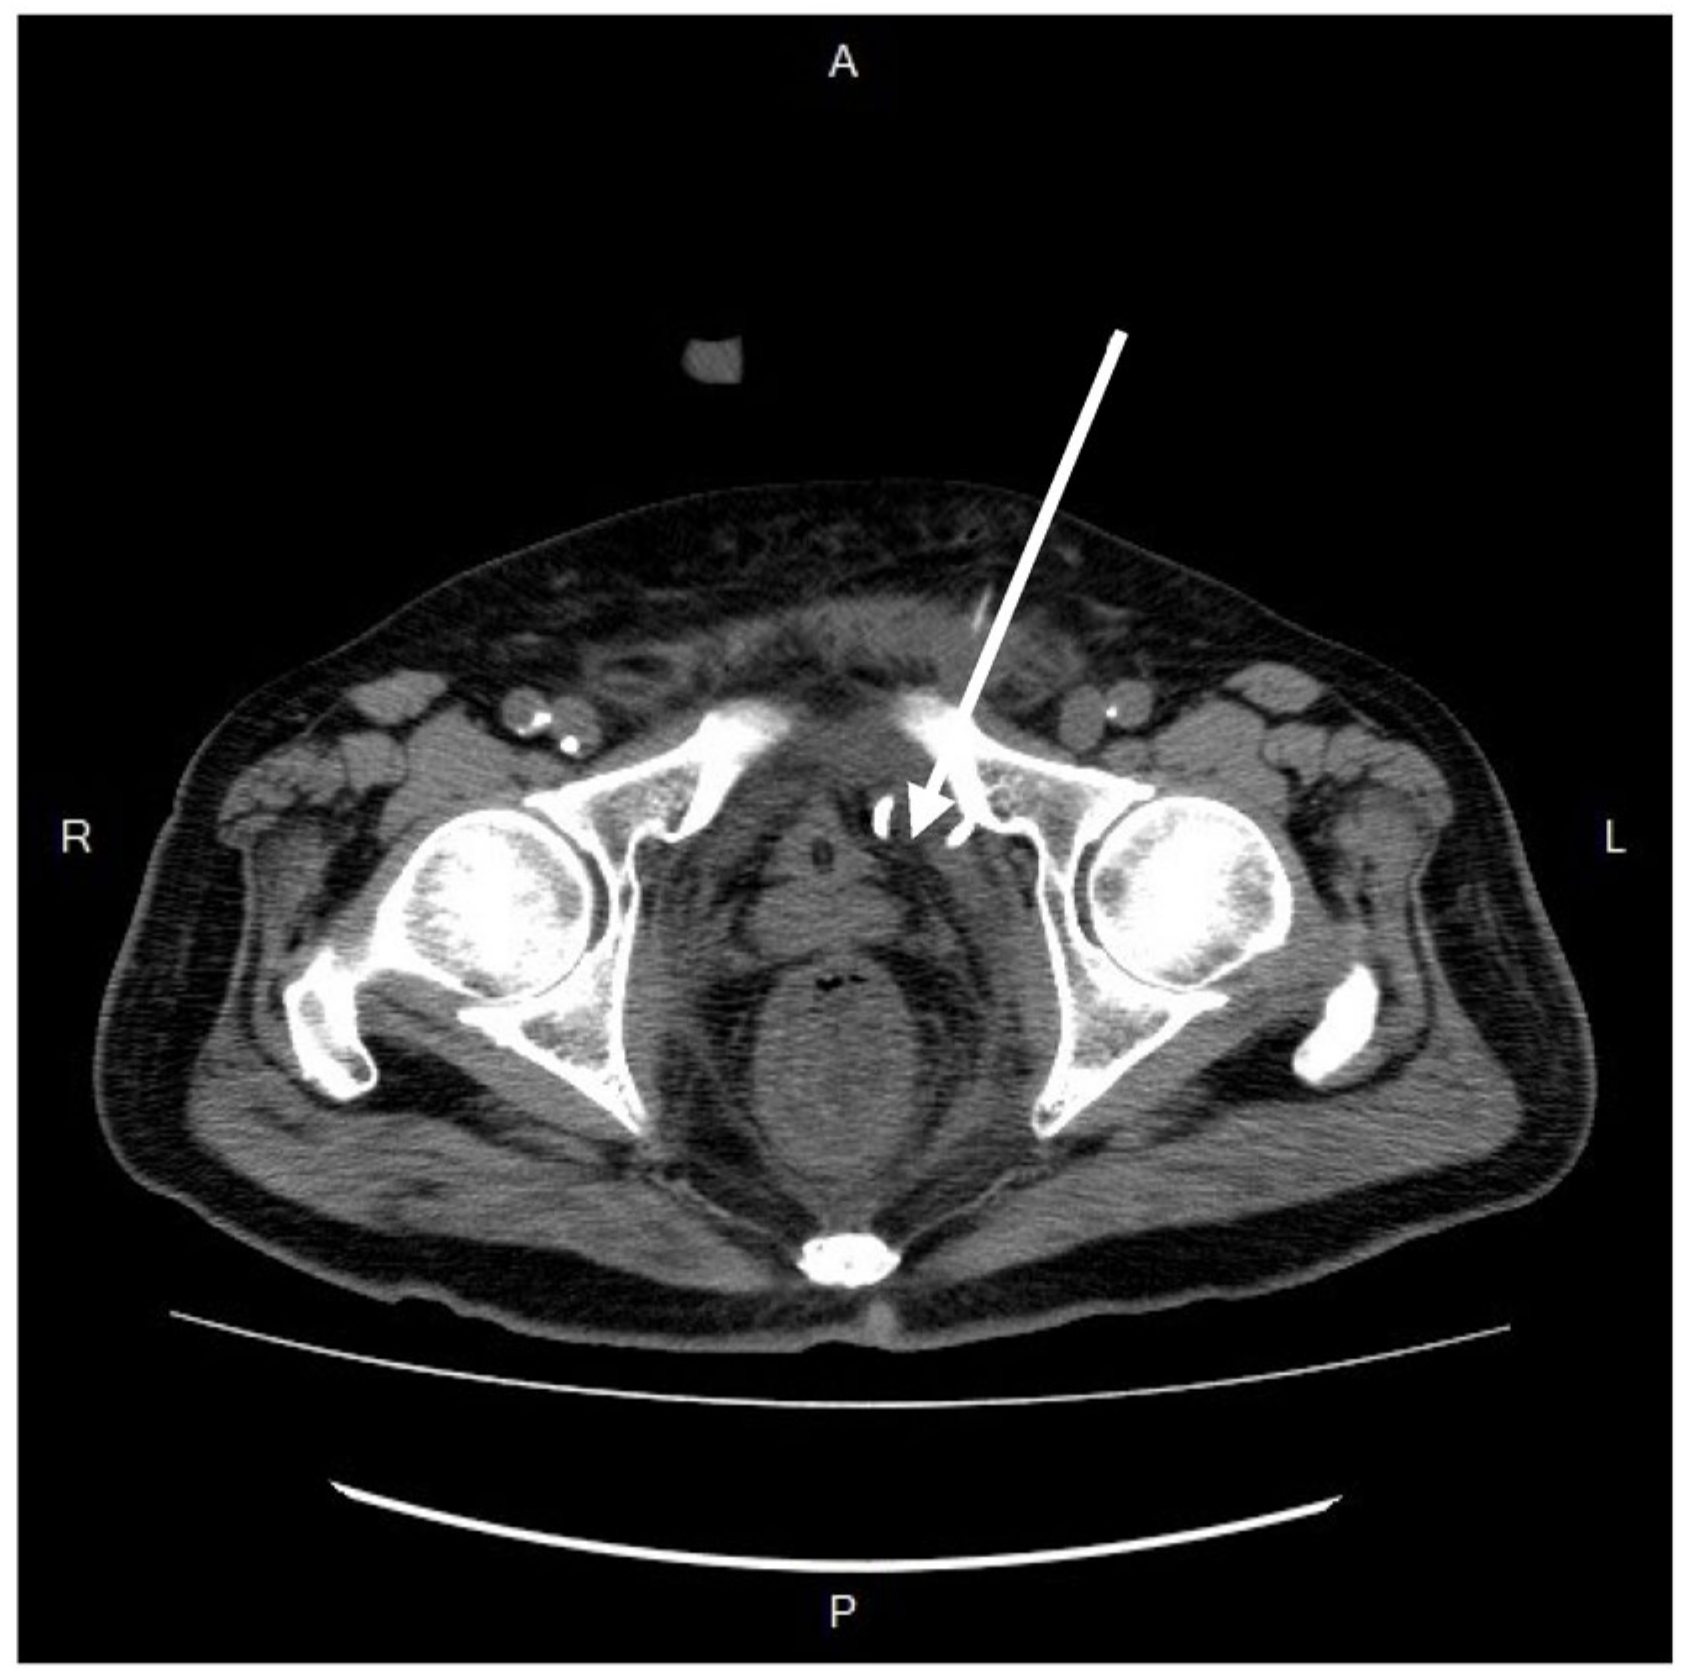

Figure 2. Axial view of contrast-enhanced computed tomography. An emphysematous collection of fluid-and-air-filled cavity (white arrow) in the perivesical space, dominantly on the left side. A Foley catheter with inflated balloon was dwelled in the bladder (red arrow). R, right; L, left; A, anterior; P, posterior.

Further diagnostic measures included a plain abdominal radiograph, which showed no pneumoperitoneum or abnormal fluid accumulation. Laboratory findings consisted of an elevated white blood cell count and C-reactive protein level (white blood cells: 27,830/μL; neutrophils: 90.6%; C-reactive protein: 21.65 mg/L). Abdominal contrast-enhanced computed tomography (CT) showed a heterogenous fluid-filled perianal abscess measuring 5.0 × 4.4 × 6.8 cm (Figure 1) in the left perianal region, with extraperitoneal air spreading through the abdominal wall fascia (Figure 2 and Figure 3). The primary abscess was situated in the supra-levator space, potentially involving the levator muscle (infra-levator), as indicated by its migration from the perianal level to the extraperitoneal level. After a comprehensive review of the patient’s symptoms, medical history, age, and current status, immediate arrangements for endoscopic tests, including upper gastrointestinal endoscopy and colonoscopy, were not made. Additionally, gastrointestinal tract specimens, such as fecal samples for calprotectin and lactoferrin, were not collected, thereby not suggesting the likelihood of inflammatory bowel diseases.

After resuscitation and blood transfusion, the patient’s vital signs stabilized, and the inotrope support was tapered. The next day, as confirmed by the CT scan and concerned about the further progression of infection, we consulted a radiologist for CT-guided extraperitoneal abscess drainage (Figure 4) and collected a significant amount of turbid fluid. Cultures from the pus were used to identify Klebsiella pneumoniae, Escherichia coli, Viridans streptococcus gr., and Bacteroides fragilis. Subsequently, antibiotic treatment with piperacillin-tazobactam was prescribed accordingly.